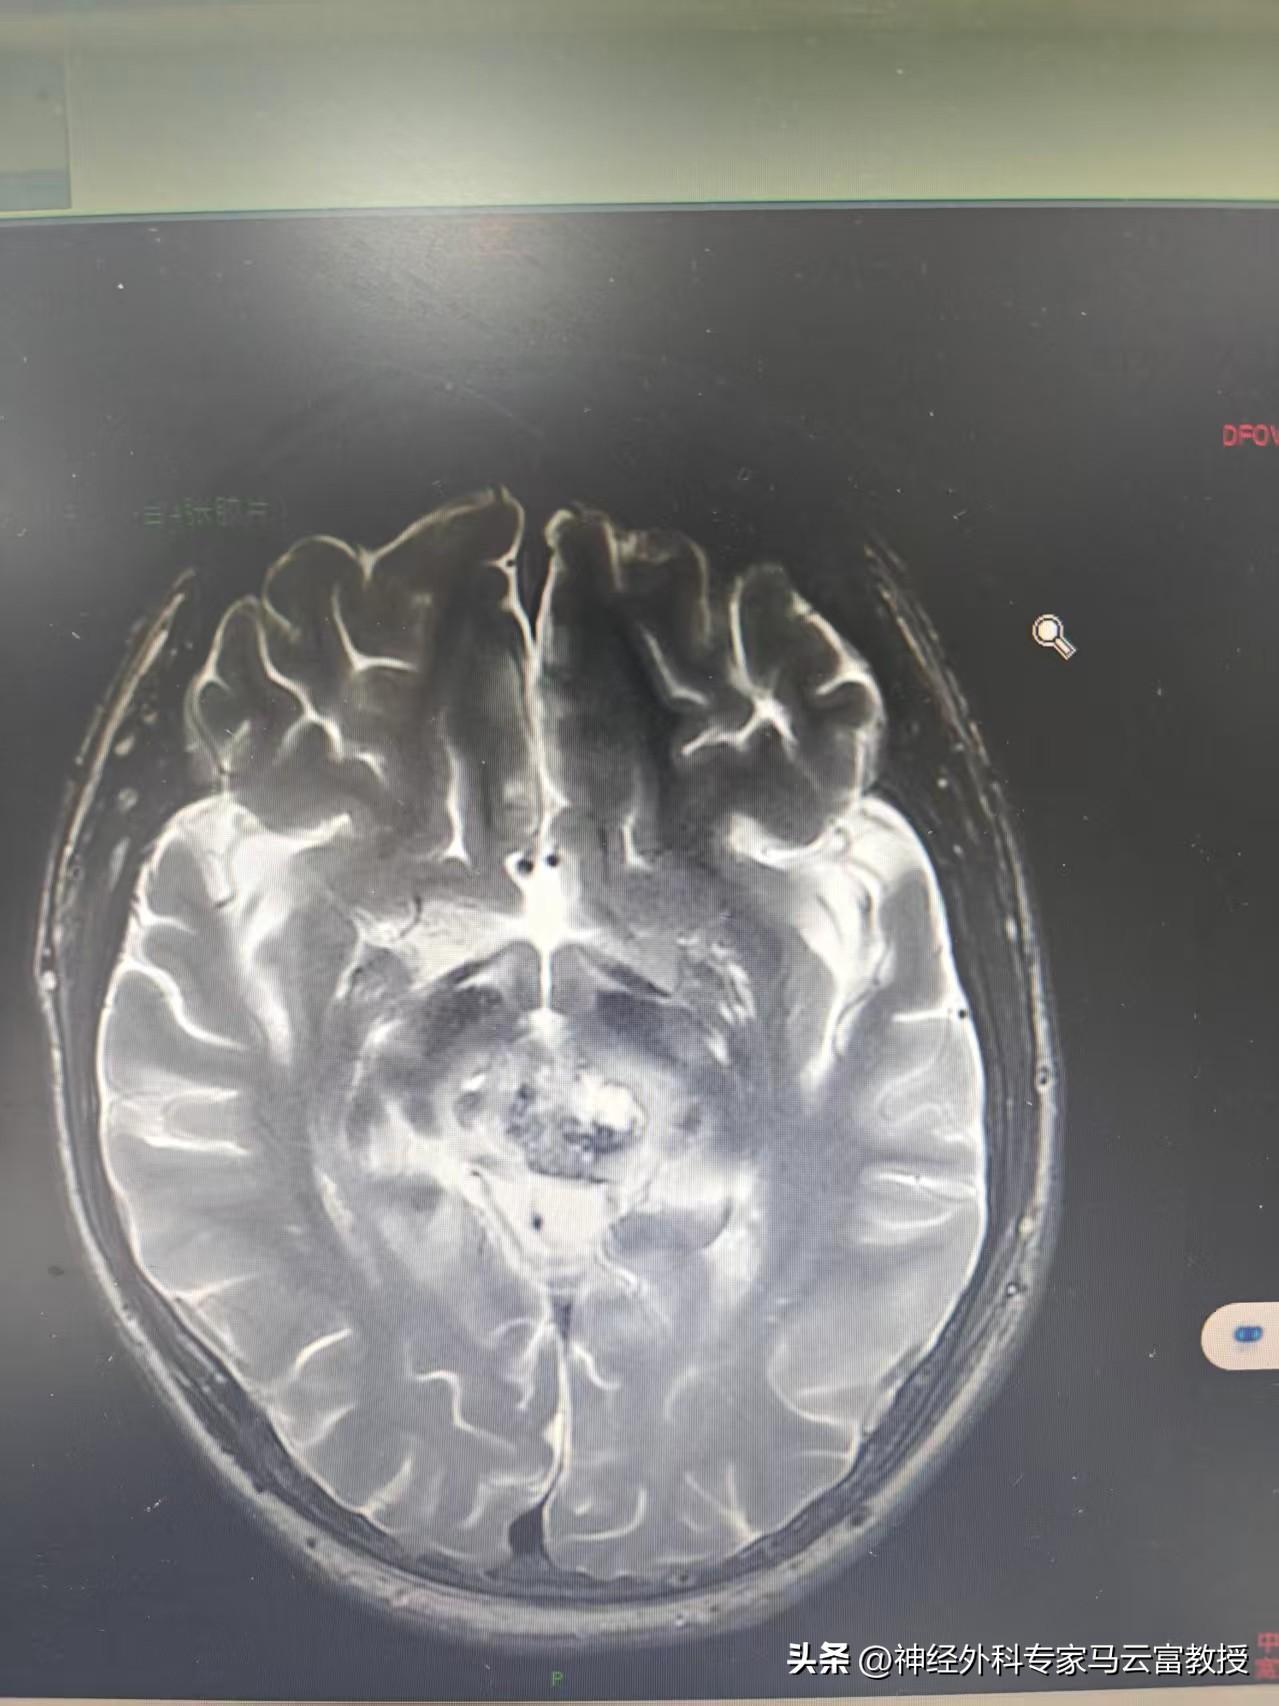

目前,小明已成功完成第一階段化療,期間未出現明顯噁心嘔吐,血常規監測亦未出現白細胞、血小板顯著下降等不良反應,身體耐受良好。近期複查頭顱MRI顯示,顱內佔位病變範圍較前有所縮小,病情初見控制成效。

第一階段化療後腦MRI